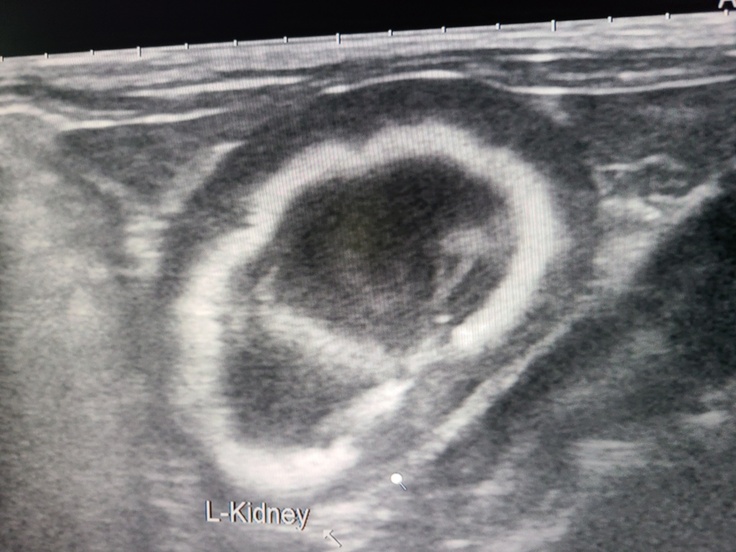

先天性または感染性の腎盂腎炎で、腎臓の形がどう見てもおかしい。左右ともボコボコ。

腎エコーの画像。

※撮影、掲載は許可を取っています。